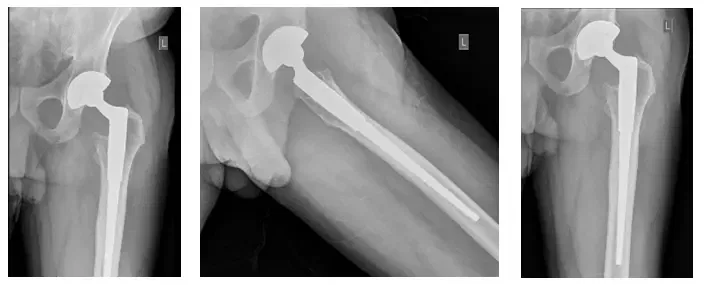

El Sr. JF es un caballero de 83 años que se había sometido previamente a un reemplazo total de cadera en otra institución aproximadamente 13 años antes de ser remitido a mí. Al principio se recuperó bien de la intervención y había estado asintomático durante gran...